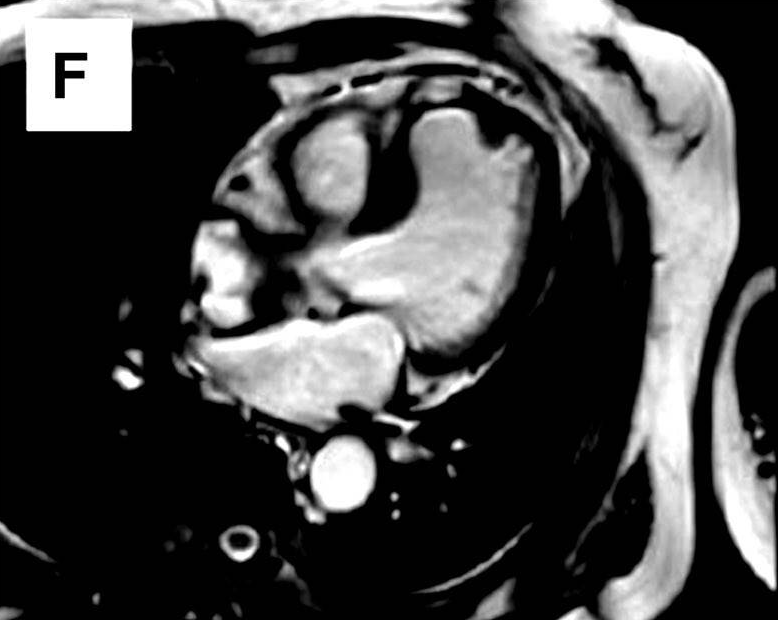

图为心电图、冠状动脉造影、经胸超声心动图、CTA及MRI检查结果。心电图显示v2-4导联T波改变(图A)。左心室造影可见室间隔肌部瘤(图C)。超声心动图显示室间隔瘤样结构(图D)。CTA与MRI均显示巨大室间隔肌部瘤(图E、F)。